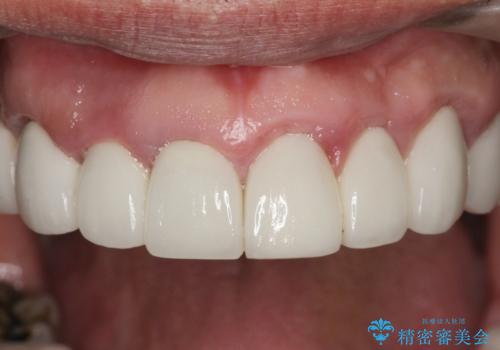

セラミッククラウンを除去し仮歯を装着し、歯周外科手術を行い歯ぐきの状態を改善したのち、適合の良いセラミッククラウンを再作製をする治療計画としました。

- 90.2万円(ジルコニアクラウン×6・仮歯×6 ・歯周外科手術)費用は治療当時の料金となります

見た目の良いクラウンが装着されていても、歯ぐきの状態が悪ければ違和感や歯ぐきの腫れ、臭いの元となっていることが多く見られます。